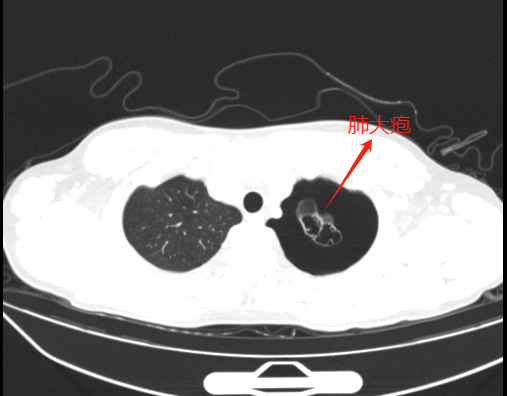

左肺多个地方都有肺大疱且呈串珠状。

由于小江肺上有多发肺大疱,若不及时进行手术治疗,气胸极易反复发作,且二次发作时肺大疱再次破裂可能导致张力性气胸,严重时甚至可能危及生命。经过与患者和家属的积极沟通,2月19日上午,王杰再次为小江实施了胸腔镜下肺大疱切除术+缝扎术及胸腔镜下胸膜固定术。术中发现,胸腔内有约200毫升血性积液,左上肺和左下肺存在多发肺大疱,最大的一个有3×2厘米,且呈串珠状。